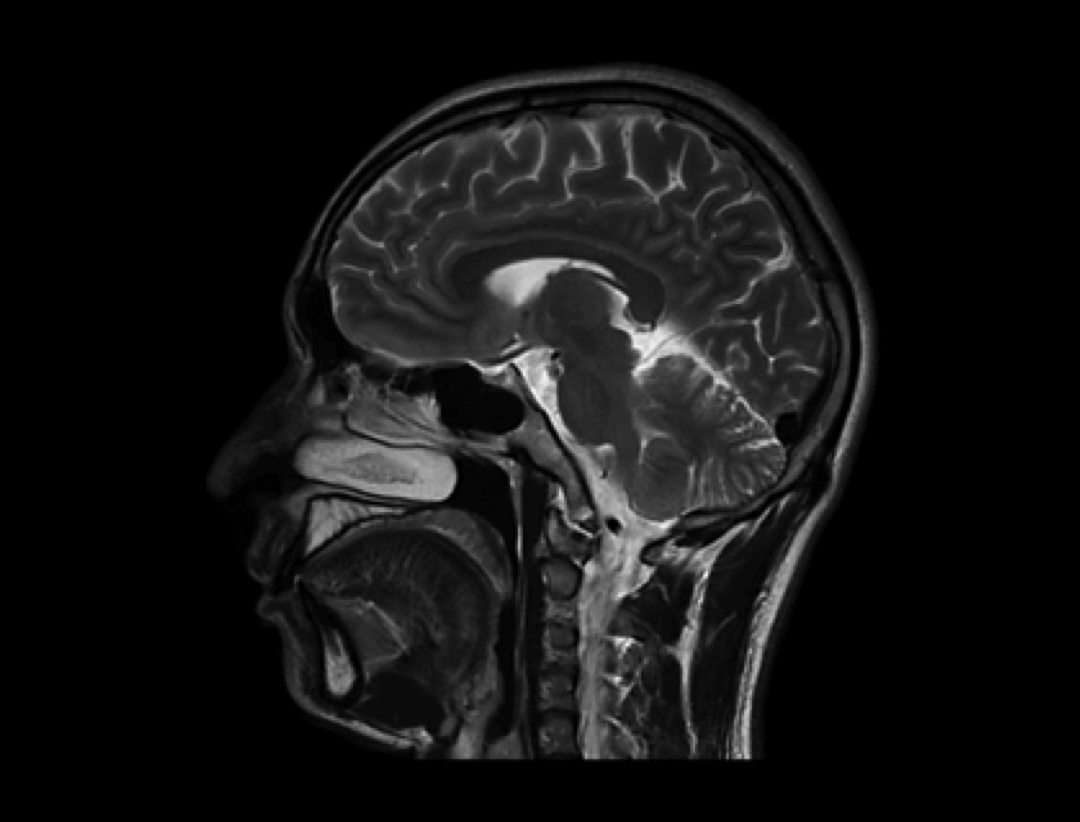

Dzięki opracowanej przez UIH technologii korekty uMR®580 cechuje się doskonałą jednorodnością pola magnetycznego.

Inteligentna technologia kompensacji prądów wirowych zapewnia wysokie parametry gradientów uMR®580.